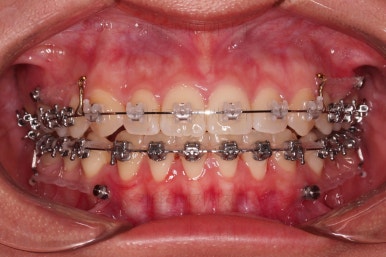

초진 시 입안의 모습입니다.

치열이 많이 삐뚠 것은 아니지만 앞니쪽이 삐뚤어 있고요. 아랫니 사이사이에 고루 틈새가 있네요.

윗니는 삐뚤고(공간부족), 아랫니는 틈새가 있다면(공간 과잉) 그 부조화는 부정교합을 의미합니다.

어금니 교합이 전반적으로 아랫니가 뒤로 빠져있는 교합이어서 맞물림이 좋지 못한 상태였어요.

장치를 부착했는데요.

윗니는 웃을 때 더 많이 보이기 때문에 세라믹 장치를 선택하셨고, 아랫니는 거의 안보이는 타입이셔서 메탈장치로 부착을 했습니다.

위아래 둘 다 자가결찰 장치였고요.

동일 회사의 장치였으며 단지 재질만 메탈이냐 세라믹이냐의 차이가 있었던거죠.